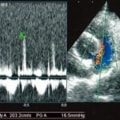

A:超音波カラードップラーでの僧帽弁逆流速度の測定

B:E波とA波の測定

C:僧帽弁逆流の動画(大きく表示させたい場合は、ココをクリックして下さい。)

症例:【マルチーズ 12歳齢 去勢オス】

左側胸壁心尖部領域を最強点とするLevine 5/6の収縮期性心雑音が聴取された。

胸部レントゲン検査において重度の心拡大と肺水腫が認められた。超音波検査では、重度の僧帽弁閉鎖不全症、三尖弁閉鎖不全症、中程度の大動脈弁閉鎖不全症を合併していることが判明した。三尖弁逆流速度から肺高血圧症が示唆された。